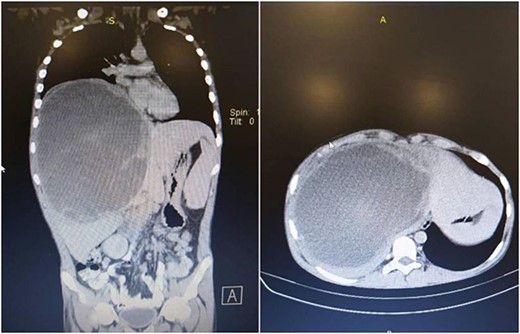

In succession, the Positron Emission Tomography (PET) Scan Multi Slice revealed a peripherally slightly metabolically active hepatic mass (205 × 134 × 208 mm) with a wide necrotic component and inactive mesenteric, retroperitoneal, and pulmonary nodes (Fig. 2).

PET Scan Multi Slice revealed a peripherally slightly metabolically active hepatic mass (205 × 134 × 208 mm) with a wide necrotic component and inactive mesenteric, retroperitoneal, and pulmonary nodes.